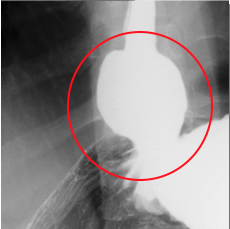

検査をすると、胃と食道の境目がゆるくて胃の一部が食道側に飛び出し(図1)、(図2)。一度胃に入ったバリウムが食道に戻ってきます(図3)。

検査中もバリウムが食道内へと逆流してきます。